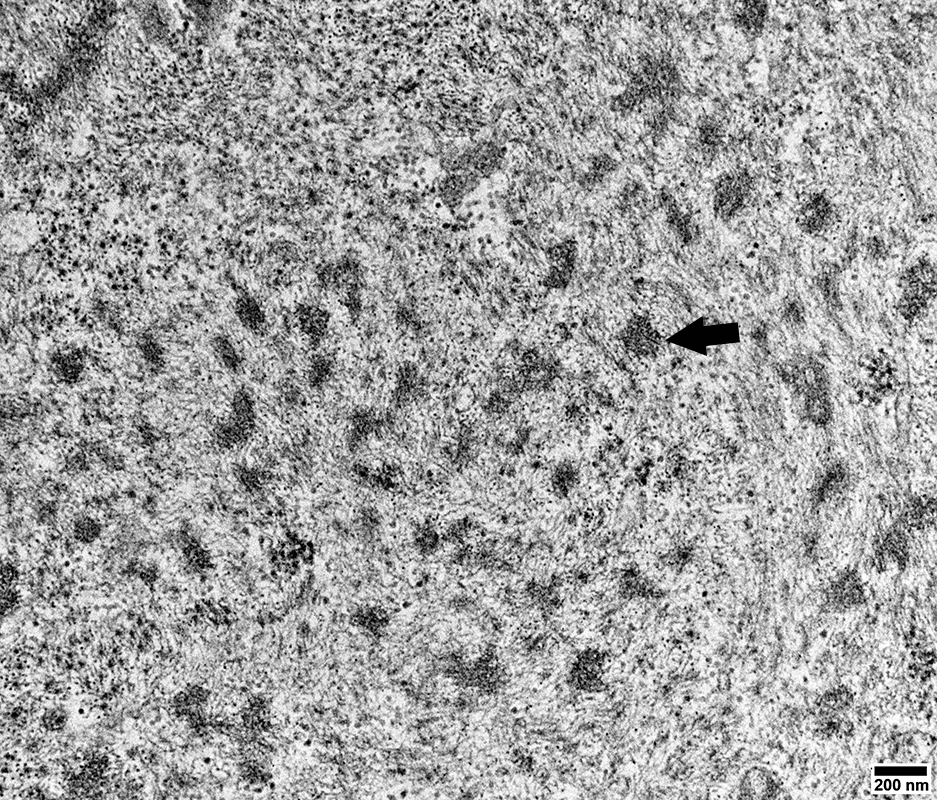

Mitochondria

Many are Small & Round (Arrow, Below)

Sarcoplamic Aggregates (Below)

Small, Irregularly shaped, Amorpohous

From: R Schmidt